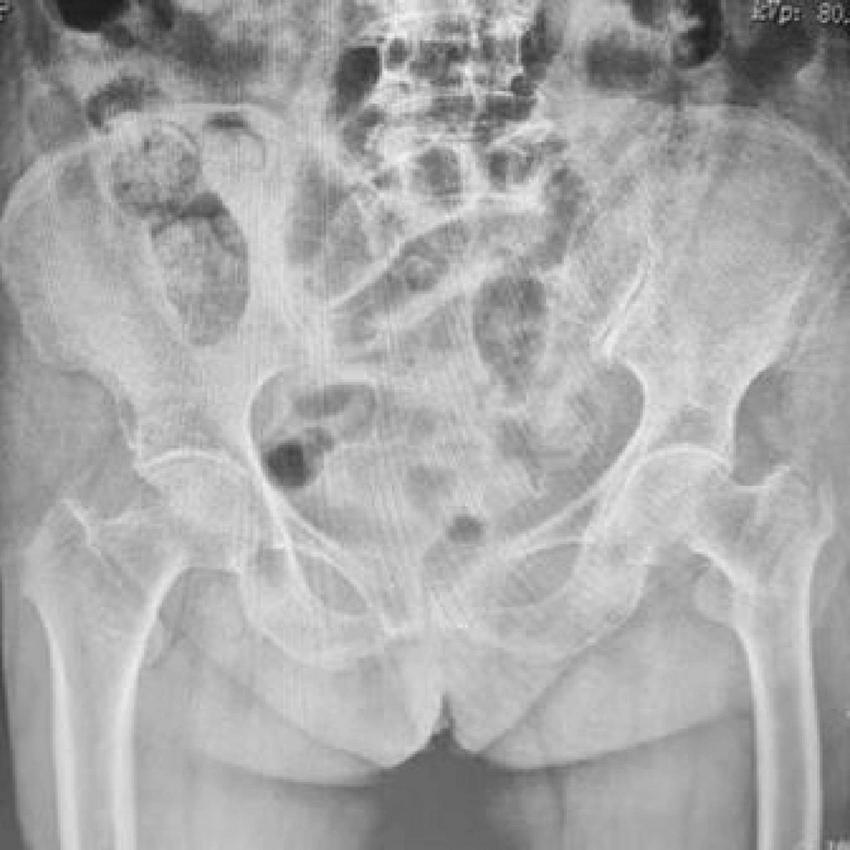

A representative case from the PFNA group involved a 78-year-old male patient who presented with right hip trauma. Preoperative imaging revealed an unstable intertrochanteric fracture (Figure 3), which was successfully treated with PFNA internal fixation, as demonstrated in the postoperative radiograph (Figure 4).

FIGURE 3

Preoperative anteroposterior radiograph of both hip joints showing unstable right intertrochanteric femoral fracture in a 78-year-old male patient. The fracture pattern demonstrates characteristic features of instability requiring surgical intervention.